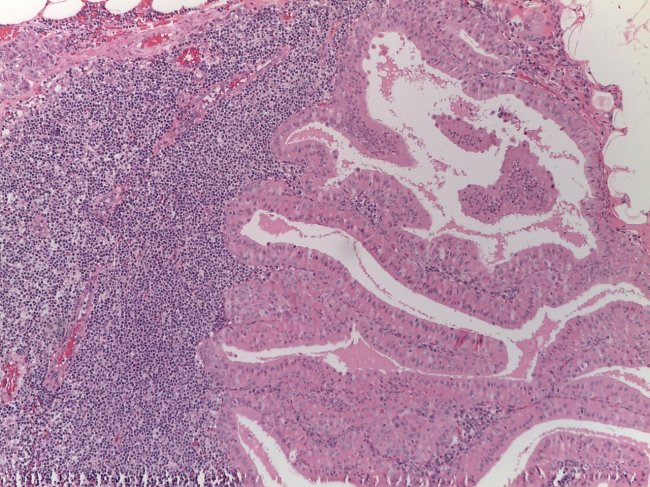

Quando a suspeita persiste torna-se necessário recorrer à biopsia para completo esclarecimento da situação. Só depois do anatomopatologista observar a colheita de tecido ao microscópio é que pode confirmar a presença de células cancerígenas.